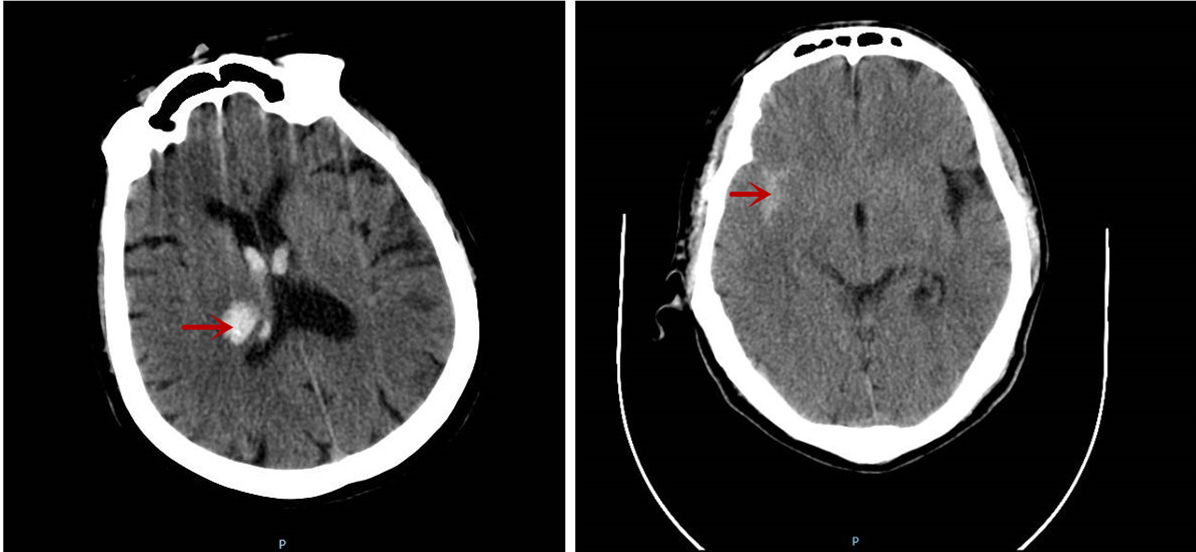

据悉,这两位患者在送医时分别呈现突发头痛伴头晕、突发肢体活动障碍等症状,经急诊颅脑CT检查,一位确诊为丘脑出血,另一位为蛛网膜下腔出血。

图中所示分别为丘脑出血及蛛网膜下腔出血情况。